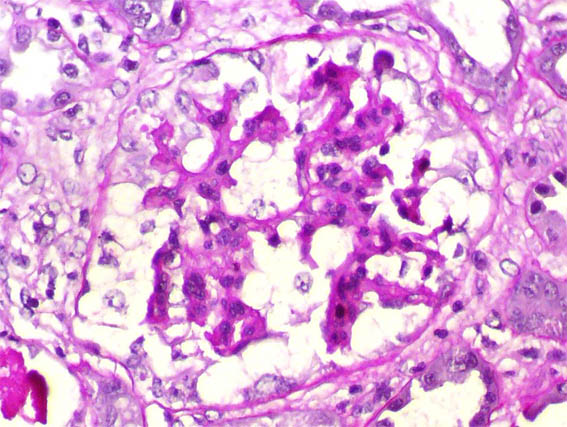

Figure 3. PAS, X400.